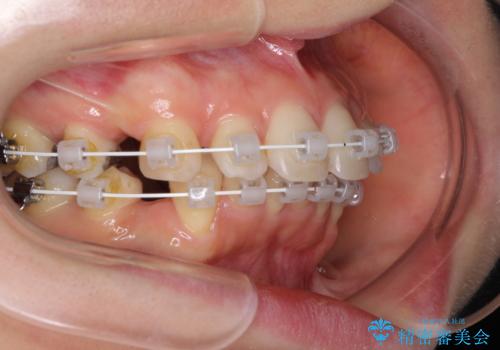

- 審美装置

- 2年8ヶ月

- 10-30回

元々ディープバイトのため、スペースを閉じている期間に上下前歯が接触してしまい、治療期間が想定よりも伸びてしまいました。